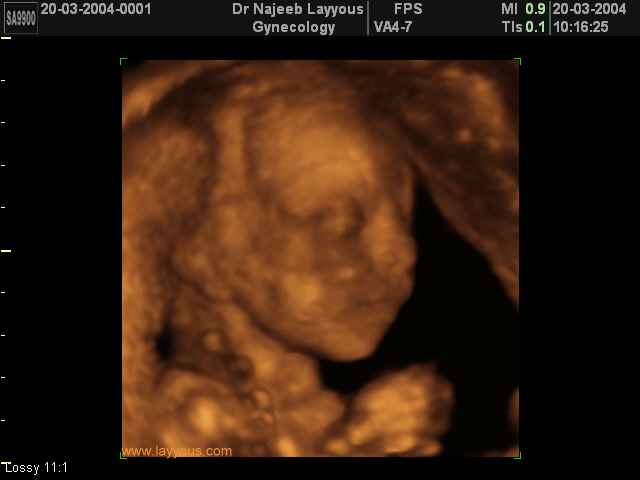

صور لوجه الجنين بجهاز الالتراساوند ثلاثي الأبعاد | الدكتور نجيب ليوس

صور لوجه الجنين بجهاز الموجات فوق صوتية ثلاثي الأبعاد